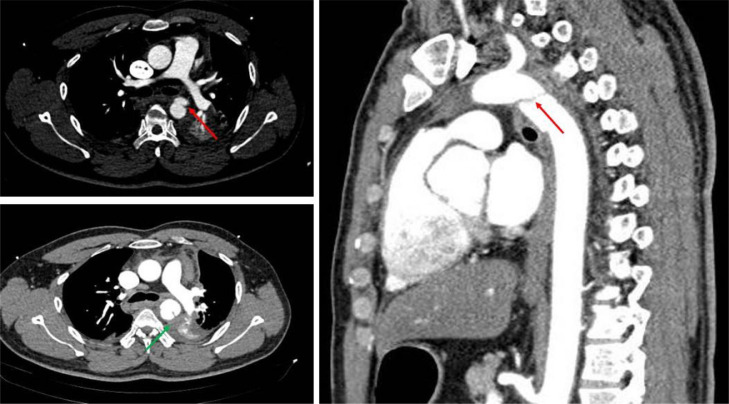

Fig. 2.

Computed tomographic angiography revealing the contour disruption, an intimal flap, luminal filling defects of descending thoracic aorta (red arrow) and periaortic hematoma formation (green arrow).